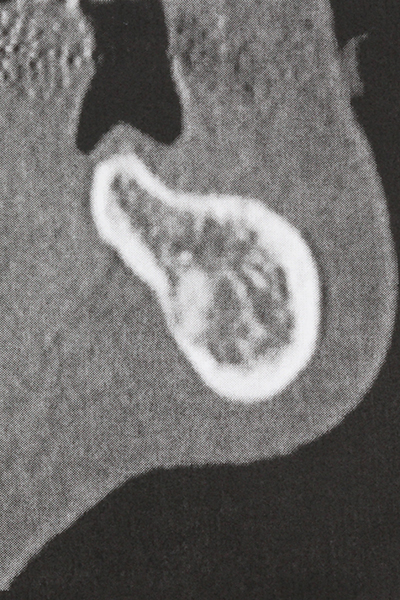

Fig. 17a: CT image of a growth-promoting osteotomy immediately adjacent to ...

Abb. 17b: the alveolar duct with nerve irritation (lateral and coronal view).